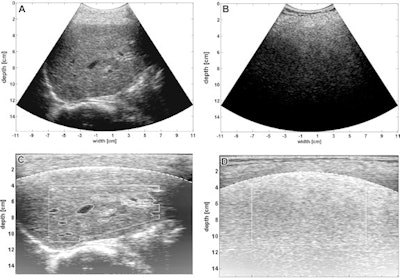

The protocol uses conventional 2D ultrasound B-mode images and semiautomatically estimates echo-level and texture parameters. The researchers noted particular interest in the residual attenuation coefficient (RAC), which is the remaining steatosis-driven attenuation gathered after beam profile correction. Data were correlated with patient characteristics, steatosis grades, and fibrosis stages.

"The method is generic, requires only a fixed imaging preset on the ultrasound system, that has been calibrated once, using a tissue-mimicking phantom," Weijers told AuntMinnie.com. "The exported 2D images obtained using this preset can be loaded and analyzed in the calibrated ultrasound software, which runs on a laptop or personal computer."

They noted a few reasons for the high performance of calibrated ultrasound in the study. For one, this method automatically assesses a large region of the ultrasound image and makes up for the normal depth-dependent behavior of the ultrasound beam and angle dependencies. As a result, it yields depth-independent analysis of quantitative ultrasound parameters.

"Further, automatic segmentation of large blood vessels and the bile duct avoids the impact of vessel wall reflections and blood signals on the calibrated ultrasound parameter," they added.